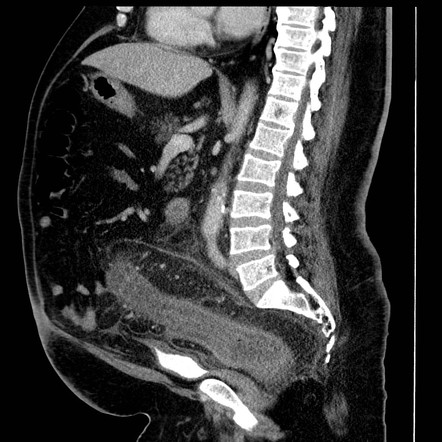

Компьютерная томография при сигмоидите хорошо выявляет следующие анатомические признаки:

В нативном режиме определяется утолщение стенки сигмовидной кишки, чаще сегментарного характера, с нарушением её нормальной дифференциации.

В режиме сканирования мягких тканей визуализируется отёк стенки, инфильтрация окружающей жировой клетчатки и возможное накопление жидкости в паракишечной зоне.

В режиме с контрастированием фиксируется интенсивное контрастное усиление слизистого слоя при снижении плотности подслизистого слоя, отражающее отёк и гиперемию.

На фоне воспаления может отмечаться сужение просвета кишки, сглаженность складок и деформация её хода.

На реконструированных срезах определяется протяжённость воспалительного участка, его влияние на соседние структуры и наличие осложнений.